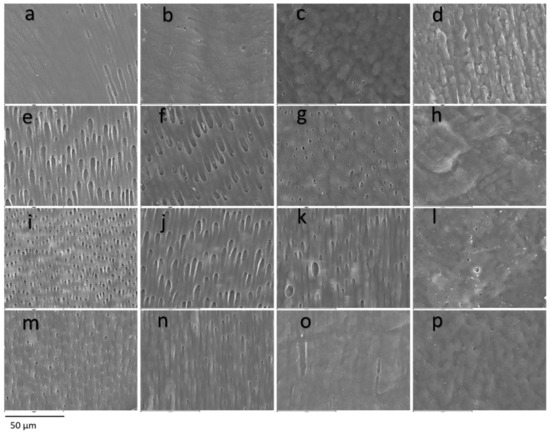

In the dentin, a generalized tissue disintegration and heterogeneity is observed with a decrease in the number of tubular dentin tubules, alteration of the diameter or tubular size, interglobular dentin and atubular areas (Figure 3). The appearance of the dentin was anomalous, with some samples showing dentin with a globular or cerebroid appearance. Significant differences were found in all the dentin points analysed compared to the control group (p < 0.001), with a higher frequency of alterations being observed in the OI group.

Figure 3.

Dentin. SEM photomicrographs at original magnification of 1000×. Superficial dentin (a–d) of a control tooth (a), dentin with mild involvement and alteration in the direction of the dentin tubules (b), dentin with moderate involvement, heterogeneity in the diameter and direction of the dentin tubules and cerebroid appearance (c) and severely affected dentin, atubular amorphous tissue with a cerebroid appearance (d). Middle dentin (e–h) of a control tooth (e) without affectation, with mild affectation (f) with heterogeneity in the diameters of the dentinal tubules, moderate with partial obliteration of the dentinal tubules (g) and severe affectation with the presence of amorphous atubular tissue (h). Deep dentin (i–l) of a control tooth (i) with homogeneity in direction and tubular diameter, mildly affected dentin (j) presenting slightly irregular diameters, moderately affected dentin (k) with the presence of giant tubules and heterogeneity in the diameter of the dentinal tubules and severely affected dentin (l) practically atubular and with an amorphous appearance. Pulpar dentin (m–p) of a control tooth (m) without alterations, of a tooth with slight alterations (n) with slight discrepancies in the tubular diameter, of a tooth with moderate alterations (o) with a decrease in the tubular pattern and of a tooth with severe alterations (p) with an atubular and cerebroid pattern.

The superficial dentin region presented alterations in 40% of the study sample, being severe alterations with amorphous structure in 16% of the samples. Severe alterations were most frequent in OI-III, followed by OI-IV and absent in OI-I. The statistical analysis revealed that the different frequencies of involvement between the types of OI are significant (Figure 3a–d) (p value = 0.012).

The middle dentin was found to be altered in 100% of the primary dentition cases of subjects with OI, the moderate alteration being the most frequent with evident involvement of the tubular pattern. Severe alteration was more frequent in subjects with OI-III or OI-IV, and in OI-I it was absent. The statistical analysis determined that the differences regarding the type of OI are not significant (Figure 3e–h) (p value = 0.09).

The deep dentin was altered in 84% of the teeth with OI, being severe with an amorphous structure in only 32% of the cases. Severe alteration of deep dentin is more frequent in subjects with OI-III than in OI-I or OI-IV. The differences in deep dentin involvement based on the type of OI were not statistically significant (Figure 3i–l) (p value = 0.149).

The dentin adjacent to the pulp was found to be altered in 92% of the teeth with OI, being severe anomalies in 56% of the occasions, and less frequently moderate or mild. Severe anomalies are more frequent in OI-III than in OI-I or OI-IV, without finding this difference significant (Figure 3m–p and Figure 4) (p value = 0.249).

Dentin has been the most studied dental structure in DGI-I and therefore the one in which most signs of structural anomaly have been described. Regarding the aetiology of dentin alterations, Majorana et al. [16] established that dentin anomalies are possibly a consequence of odontoblast dysfunction, and Lygidakis et al. [17] hypothesized that tubular obliteration is due to mineralization. Multiple investigations have described ultrastructural findings of dentin [16,17,19,24,25,26,29,31,32,33], which can be summarized in the presence of irregular dentinal tubules with alterations in their direction and the presence of both giant and obliterated tubules with circular areas of intertubular matrix without calcification. Similar ovoid areas embedded in dentin have been observed in studies in type II DGI, but it is unclear whether they are unmineralized areas or giant or irregular tubules that have fused together [34]. In addition, the alternation of areas of apparently normal dentin and regions with abnormal dentin has been described. These findings are consistent with our results, in which we found very similar images of varying severity in the four dentin points examined, corresponding to the presence of dentin tubules with a very heterogeneous pattern, with changes in tubular diameter, reduction in tubular density with the presence of atubular regions or with remnants of obliterated tubules, presence of giant tubules and, in the most severe cases, images of totally dysplastic, amorphous and atubular dentin with a globular or cerebroid appearance, which is similar to the findings previously described by other authors.

Malmgren and Lindskog [18] created a dysplastic dentin scale through clinical–radiographic assessment; their findings indicated that the dentin presents greater dysplasia in the circumpulpar area than in the mantle dentin. In addition, they did not find differences in affectation between the primary and permanent dentition. De Coster [28] and Hall et al. [10] analysed the dentin at different depth points, establishing that the mantle dentin and the first layer of tubules is apparently normal, ending abruptly in a zone parallel to the UAD in the which obliterated tubules are found and from which normal and dysplastic or atubular areas alternate. Our data indicate that all the teeth show dentin involvement in at least one point of their extension. Regarding our results, based on the depth of analysis, the dentin closest to the DEJ is the least frequently altered in subjects with OI (40%), being followed by a layer of dysplastic dentin in all cases, leaving passage to the deep and pulpar dentin altered in 84% and 92% of cases, respectively.

Type I collagen is altered both systemically and dentally; therefore, a correlation could be established regarding the severity of the dysplasia. However, collagen does not have the same function in bone and dentin, so the severity of bone and dentin involvement is highly variable [15]. Some authors established that there are no dental histological differences between the different types of OI [16], while others [18,28] established that there are morphological differences in dentin, with more frequent and marked findings in patients with OI type III and IV than in type I. Malmgren and Lindskog [18], despite observing that the manifestations of dysplasia in the mantle dentin increase with the severity of the OI, did not find a relationship between the type of OI and dysplasia dentin. Derived from our results, we can affirm that, in general, more severe dental morphological anomalies are found in subjects with a more severe phenotype of the disease. By differentiating four regions of different depths of dentin, we found a significant relationship between dental and systemic severity in superficial dentin, although in all the areas studied anomalies were found more frequently in subjects with more severe OI.